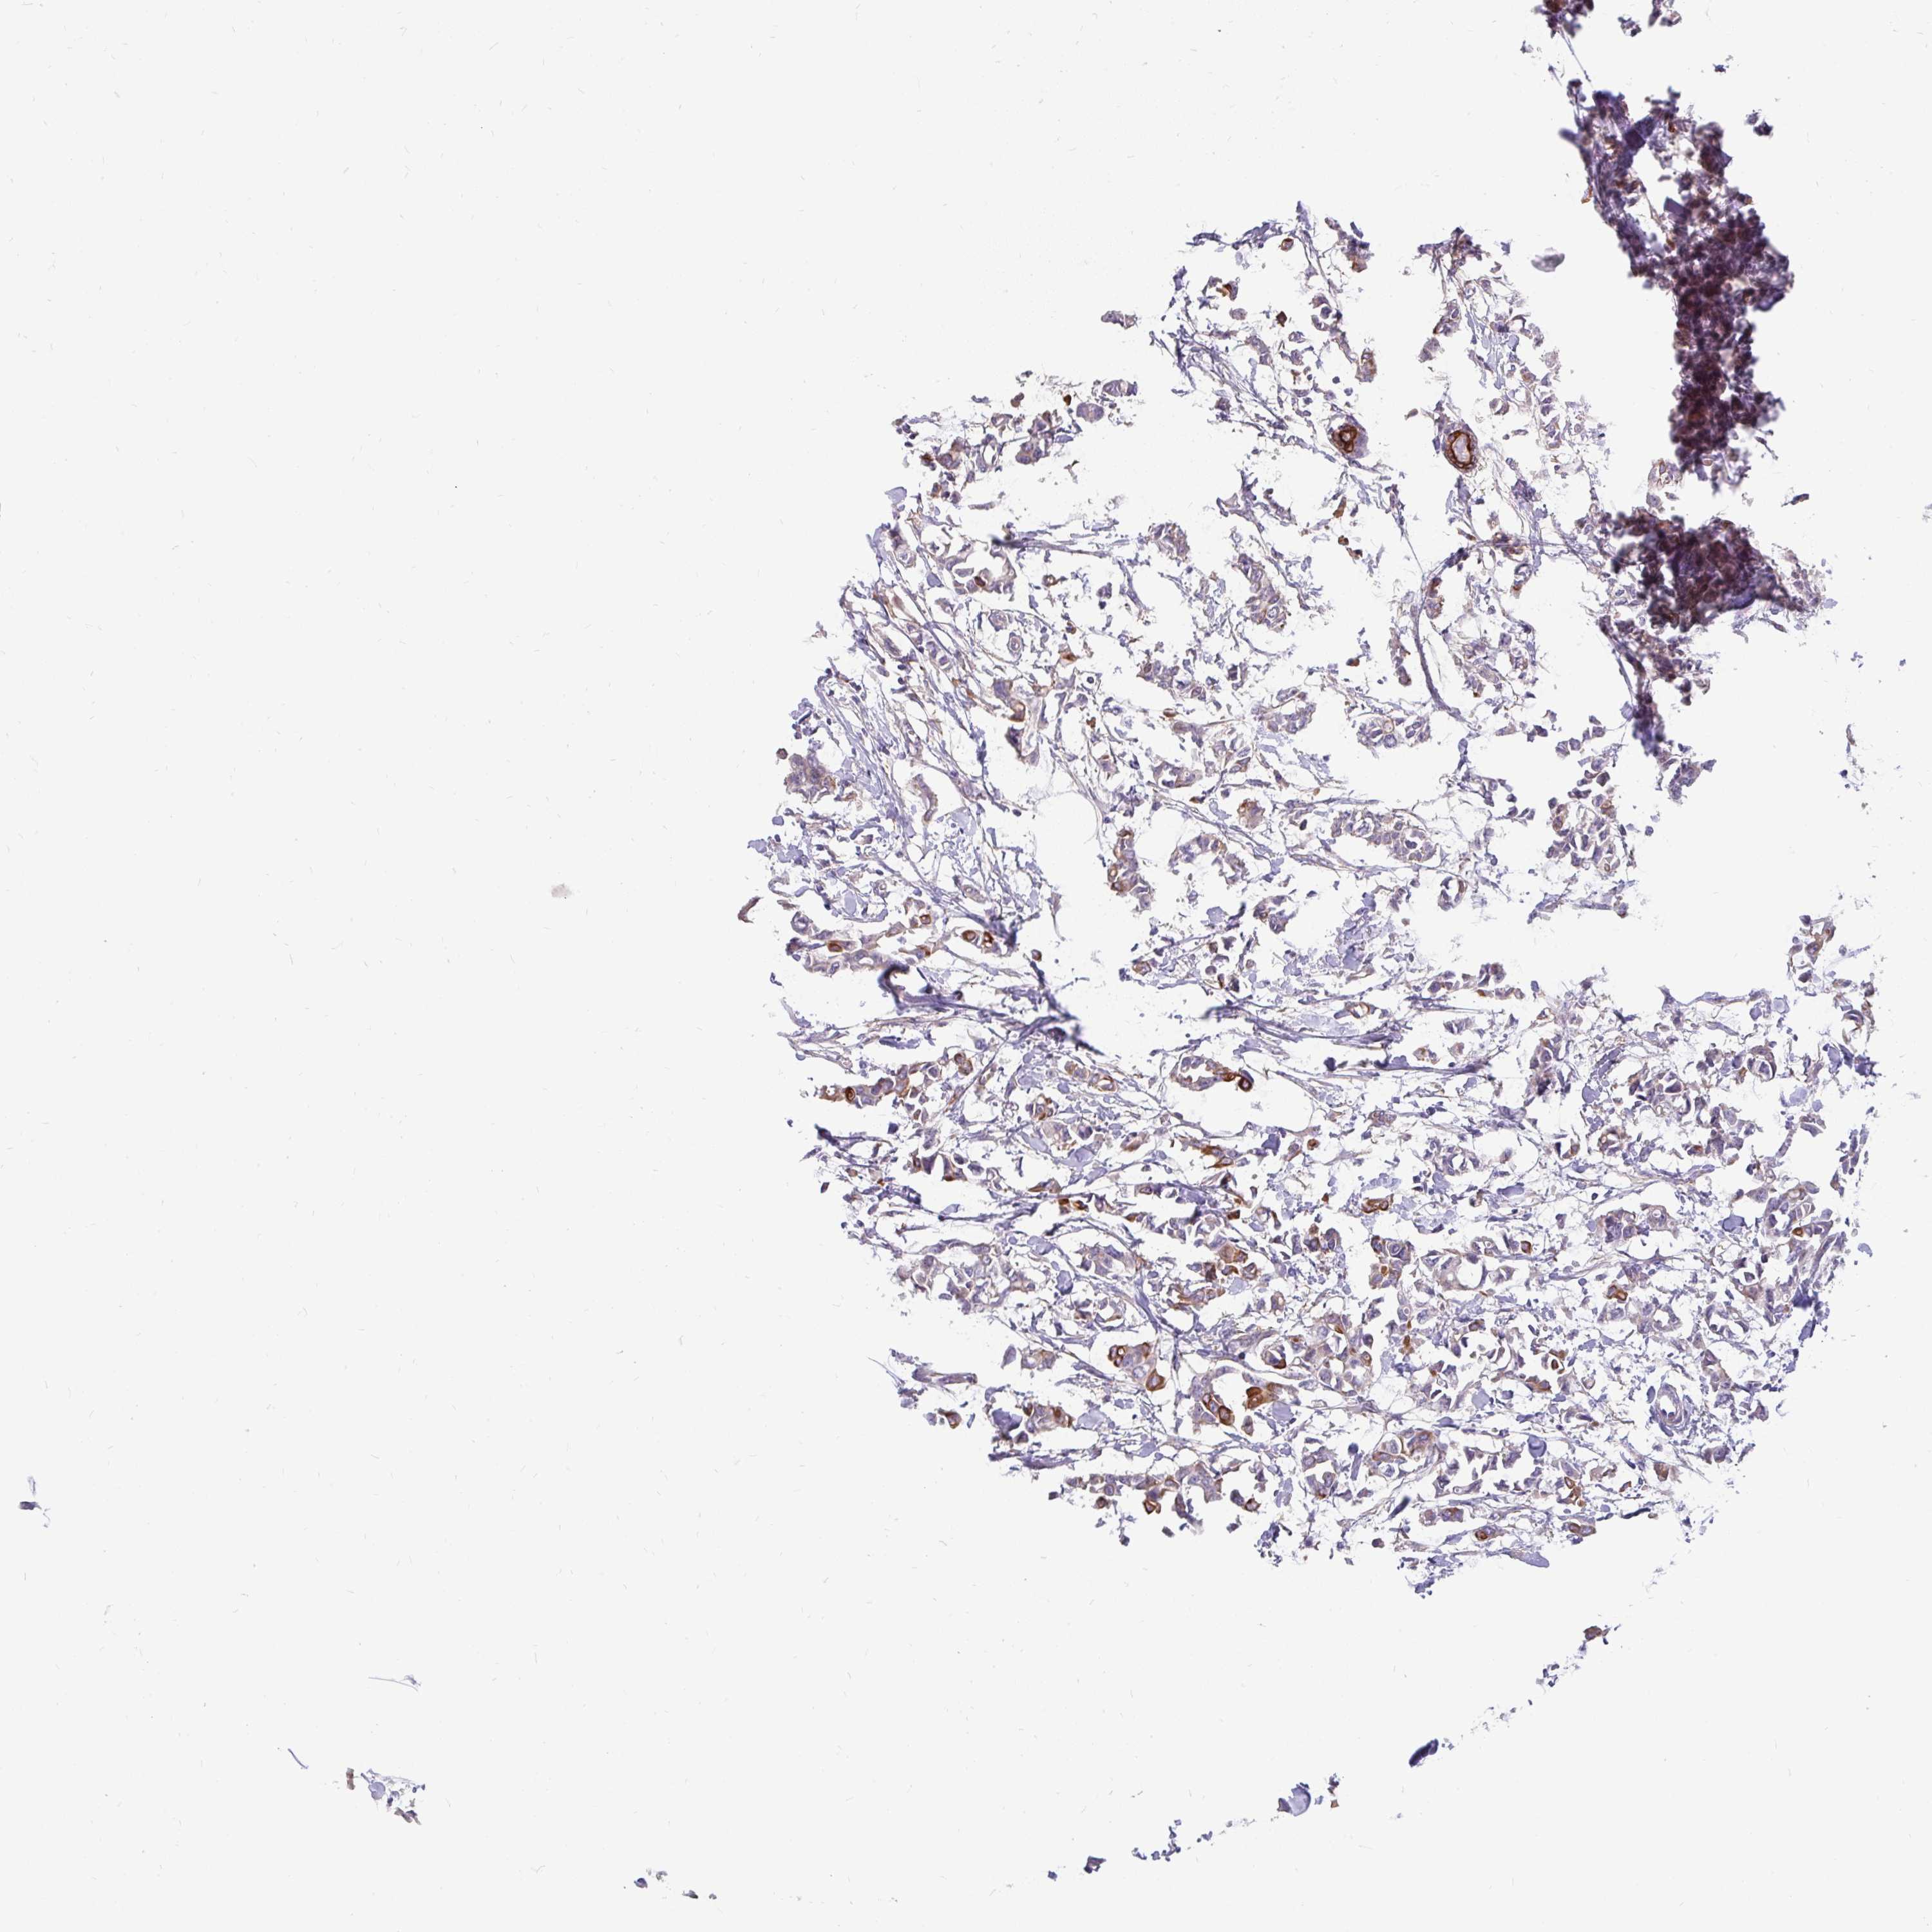

CANCER BREAST CANCER Show tissue menu

BRCA TCGA BRCA VALIDATION PROTEIN EXPRESSION